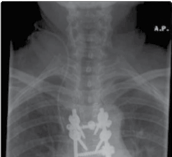

Figure 4.2 Thoracic vertebrectomy with posterior stabilisation for a solitary metastasis.